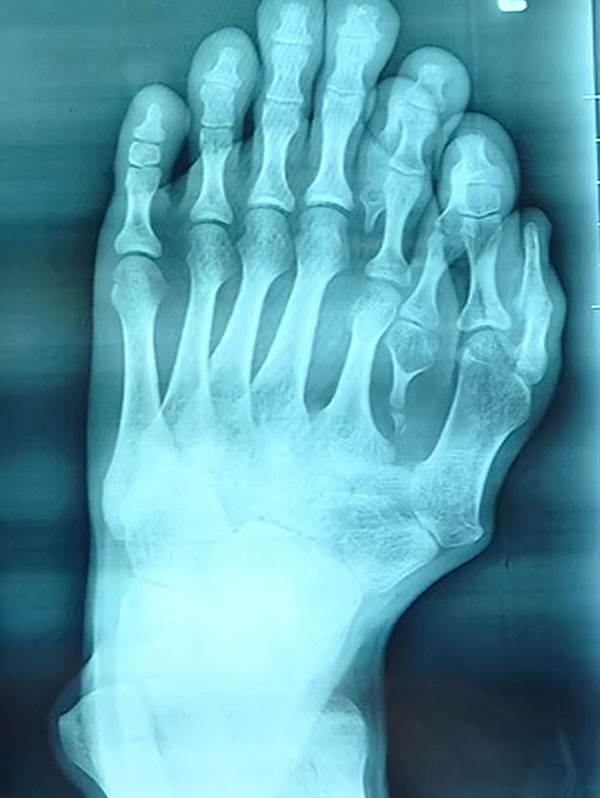

ในที่สุด เมื่ออาจุนเข้าสู่วัยผู้ใหญ่ สามารถตัดสินใจได้ด้วยตัวเอง เขารีบขอความช่วยเหลือทางการแพทย์ ซึ่งเมื่อแพทย์ทำการเอกซเรย์พบว่า ความผิดปกติมีความรุนแรง นิ้วเท้าขนาดเล็กงอกแทรกระหว่างนิ้วเท้าปกติในลักษณะแปลก และเขาไม่มีนิ้วโป้ง กลับแทนที่ด้วยนิ้วสองนิ้วเป็นรูปตัววี